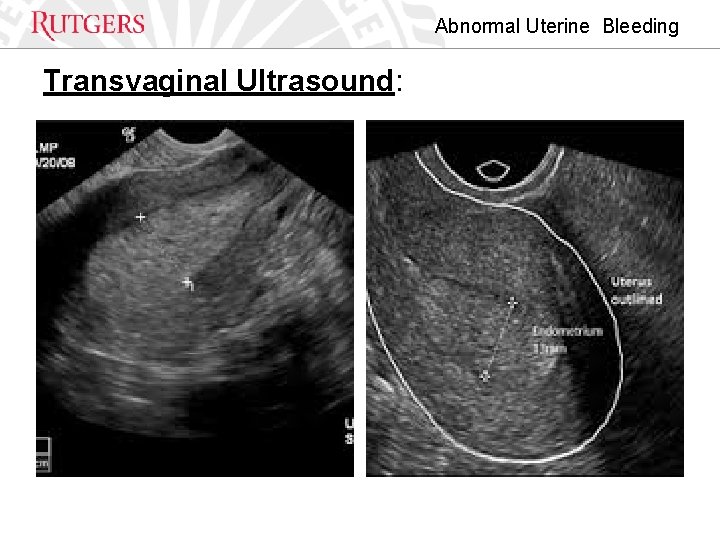

Abnormal Uterine Bleeding Transvaginal Ultrasound:

Abnormal Uterine Bleeding Endometrial Biopsy NICE recommends endometrial sampling in women with • Persistent inter-menstrual • Bleeding or aged 45 years with treatment failure • Excise clinical judgement for those women aged <40 years with HMB at risk for premalignant changes Obesity PCOS NICE. Clinical Guideline 44; Heavy menstrual bleeding 2007. National Institute for Health and Clinical Excellence (NICE); • Available at: http: //www. nice. org. uk/nicemedia/pdf/CG 44 Full. Guideline. pdf.

Abnormal Uterine Bleeding Endometrial Hyperplasia Progressing to Endometrial Cancer • Simple Hyperplasia 1% • • Complex Hyperplasia 3% • Simple Hyperplasia • w/Atypia 8% • Complex Hyperplasia • with atypia 29 % • Incidence of endometrial cancer -147 per 100, 000 women in Ghana • • • "In 159 cases (90%), the endometrial histologic results of curettage agreed with those of the Pipelle biopsy. All three cases of endometrial cancer were identified by Pipelle aspiration. In seven cases (4%), the Pipelle aspiration failed to detect hyperplasia. Sonographic endometrial thickness of more than 5 mm slightly increased the sensitivity and slightly decreased the specificity of Pipelle aspiration from 82 to 92% and from 99 to 96%, respectively Goldchmit R. Katz Z. Blickstein I. Caspi B. Dgani R. The accuracy of endometrial Pipelle sampling with and without sonographic measurement of endometrial thickness. Obstetrics & Gynecology. 82(5): 727 -30, 1993 Nov. Abstract. Full text available to Fellows, Members and Trainees here. Kavak Z, Ceyhan N, Pekin S. Combination of vaginal ultrasonography and pipelle sampling in the diagnosis of endometrial disease. Australian and New Zealand Journal of Obstetrics and Gynaecology 1996; 36(1): 63– 6. Abstract. Map of Medicine. Endometrial cancer. 2011.